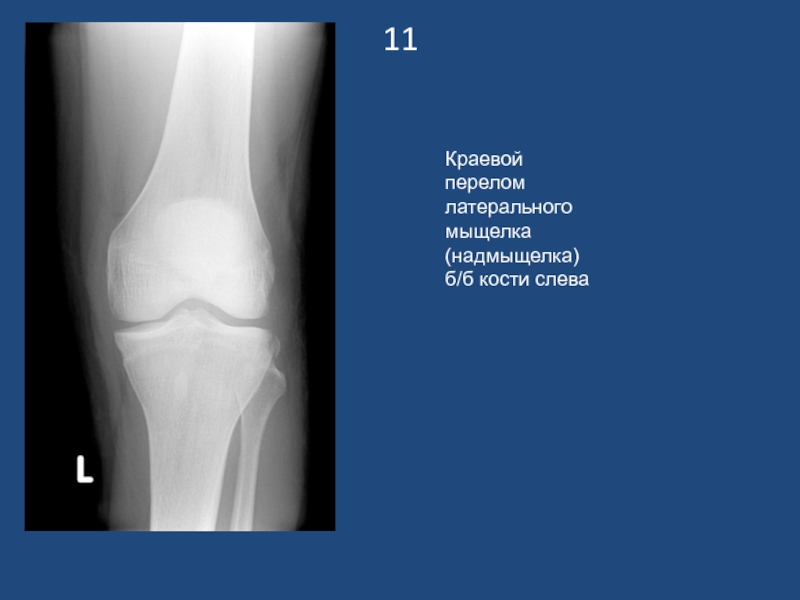

Краевой перелом латерального мыщелка (надмыщелка) б/б кости слева

11Краевой перелом латерального мыщелка (надмыщелка) б/б кости слева